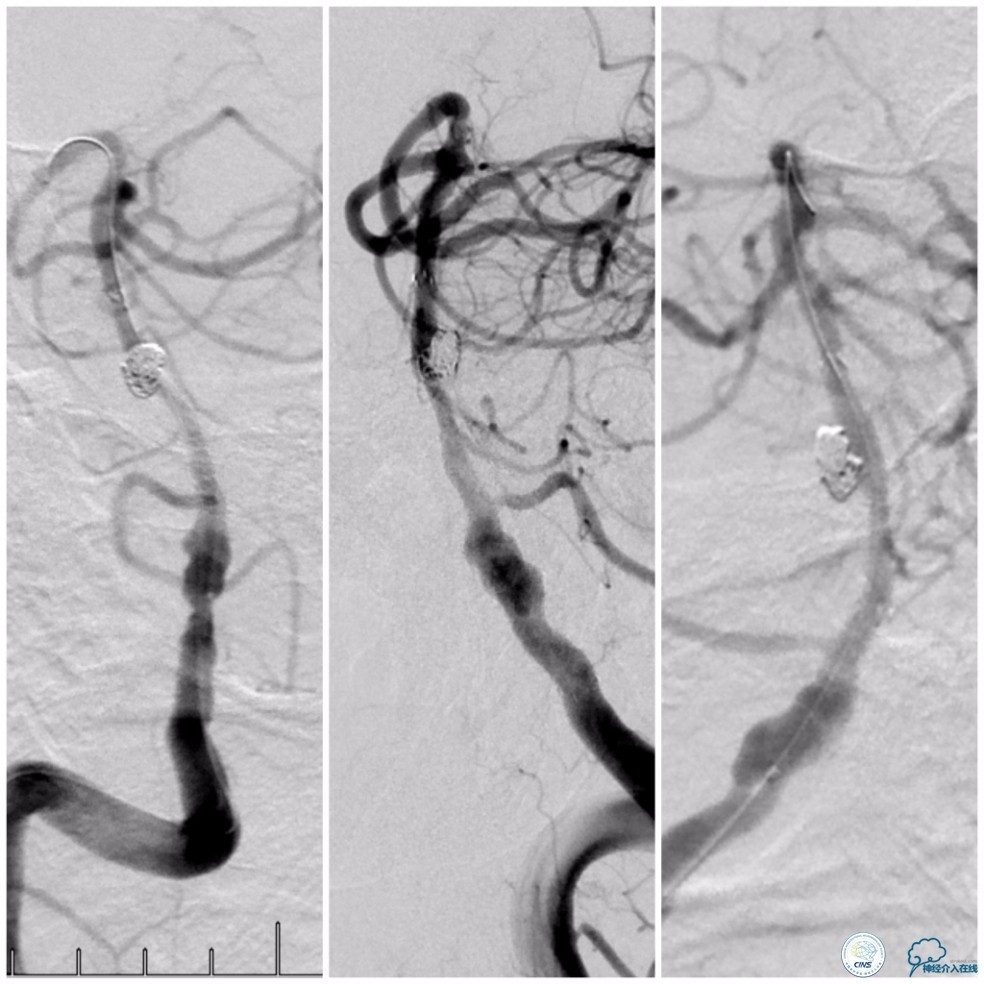

沿Echelon-10微导管依次推入EV3 PC-3-6-3D 3mm×6cm、QC-3-6-3D 3mm×6cm、QC-2-6-3D 2mm×6cm、QC 1.5-2-HELIX 1.5mm×2cm四个弹簧圈进入动脉瘤腔内。造影显示动脉瘤腔填塞致密(图12)。

图12

撤出Echelon-10微导管及5F导引导管。沿6F导引导管送入Select Plus微导管至基底动脉远端。经微导管送入Enterprise 4.5mm×28mm至右椎动脉V4段,两个支架重叠约2-3mm,完全覆盖右椎动脉V4段夹层(图13)。

图13